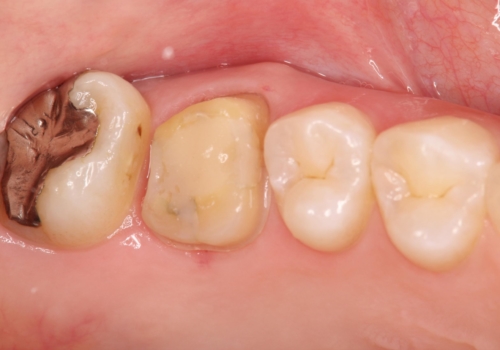

根の神経の治療を行い、セラミックを装着する計画としました。

根の神経が細菌に感染するとこのように、膿の出口ができることがあります。

その場合は、根の中の治療(根管治療)が必要になります。